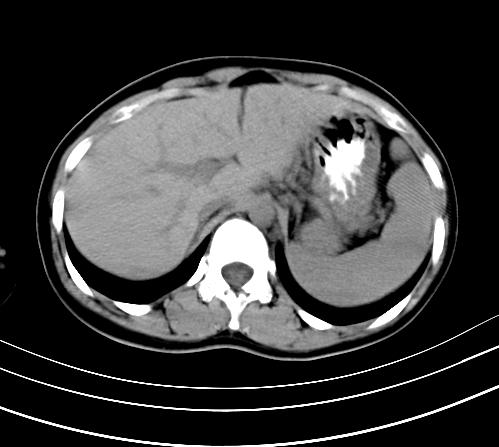

腹部平扫